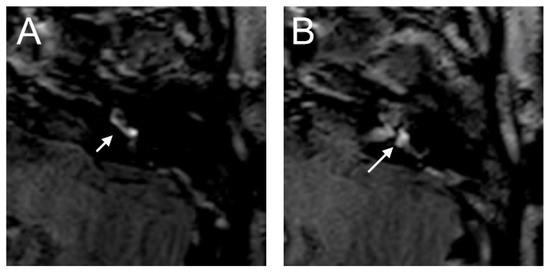

The VHIT showed a decreased VOR gain of the left anterior (0.00) and left posterior (0.33) canals, whereas the other VOR gain was preserved (>0.85). Moreover, a profound left canal paresis was observed with caloric tests. Intraoperatively, the round niche was wet, but CTP testing was negative. The contrast enhancement was seen in the left vestibulum and cochlea, and a SURI was observed here on the delayed postcontrast 3D-FLAIR sequences, suggesting vestibular endolymphatic hydrops, grade I (Figure 8). In the CT image, a dehiscence of the superior semicircular canal on the right side could be identified, but these could not be detected with contrast enhancement on the 4 h delayed 3D-FLAIR sequence. On in the T2W image was a hypointense signal intensity observed in the cochlea.

Figure 8. An 85-year-old female presented with sudden hearing loss on the left side with rotatory vertigo. The contrast enhancement was seen in the left cochlea ((A) dashed arrow) on the axial 4 h delayed 3D-FLAIR sequences. The inversion of the saccule ((A) arrow) to the utricle ((B) arrow) area ratio was observed.